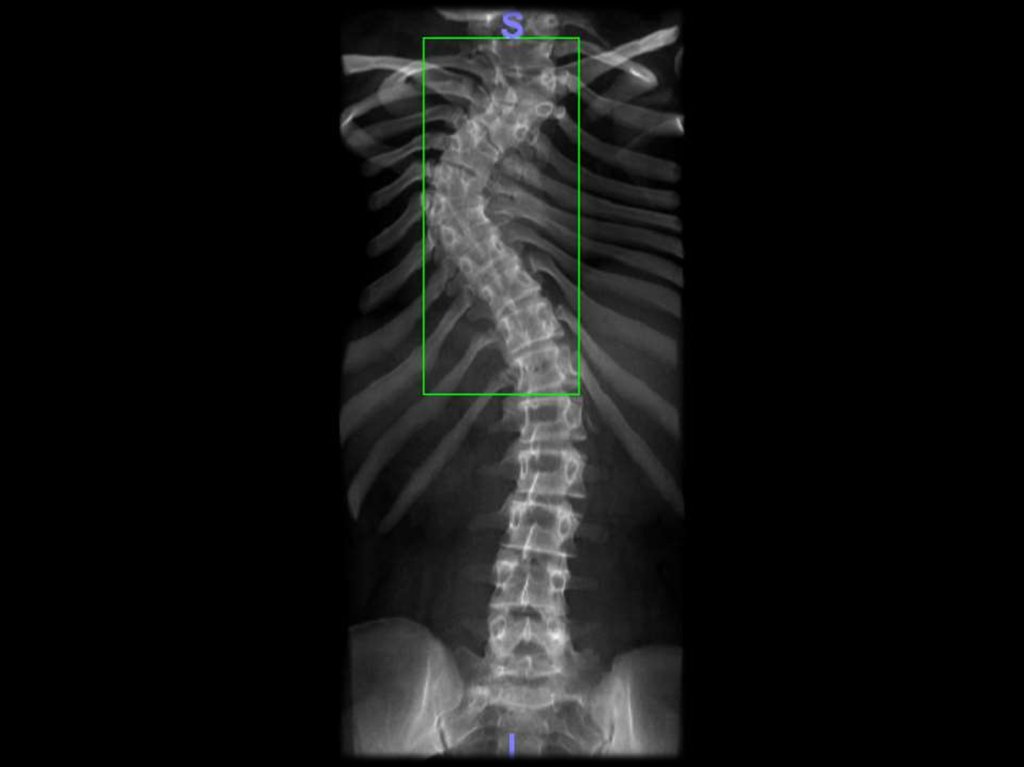

СКОЛЕОЗ ГРУДНОГО ОТДЕЛА